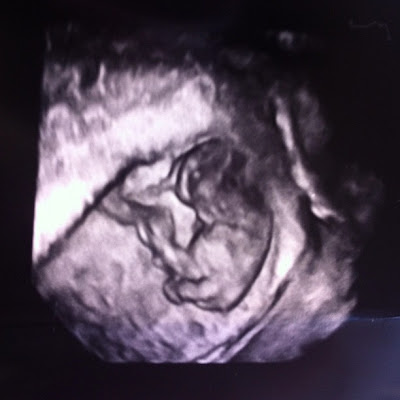

| At nine weeks Baby B is blurry due to constant movement, while Baby A is calm and relaxed. |

It was surreal to see the two of you in our first ultrasound. That was, of course, the first time we were officially told we were having twins. In our second ultrasound, it was crazy to see how much you have already grown. I’m told you are the size of an olive at nine weeks. Even at that size, your little heads, arms, legs, round bellies and umbilical cords were clearly seen in the ultrasound. When you first appeared on the screen, the first words out of our doctor’s mouth were, “Wow they are really growing and getting big!” This might also explain why I am already starting to show so early in my pregnancy. The nine week ultrasound may have also given us our first glimpse into your individual personalities. Baby A was very still in all of our pictures and seemed to be calm, cool and relaxed. In fact, Baby A had a perfect pose for the 3D ultrasound picture. I’ll be curious to see if you stay this way, and if you do indeed have your father’s low-key personality. Baby B, on the other hand, seemed less content. You moved around the entire time they were probing me and trying to get some pictures. You are blurry in every single one of your pictures, because you were moving so much! In your 3D ultrasound, you look like a gummy bear rather than a baby, due to your constant movement! I’ll be curious to see if you were just active during the ultrasound, or if your personality is just busier than Baby A and a little less content. If so, you take after your mother.

| Baby A 9 week 3D ultrasound |

| Baby B 9 week 3D ultrasound |